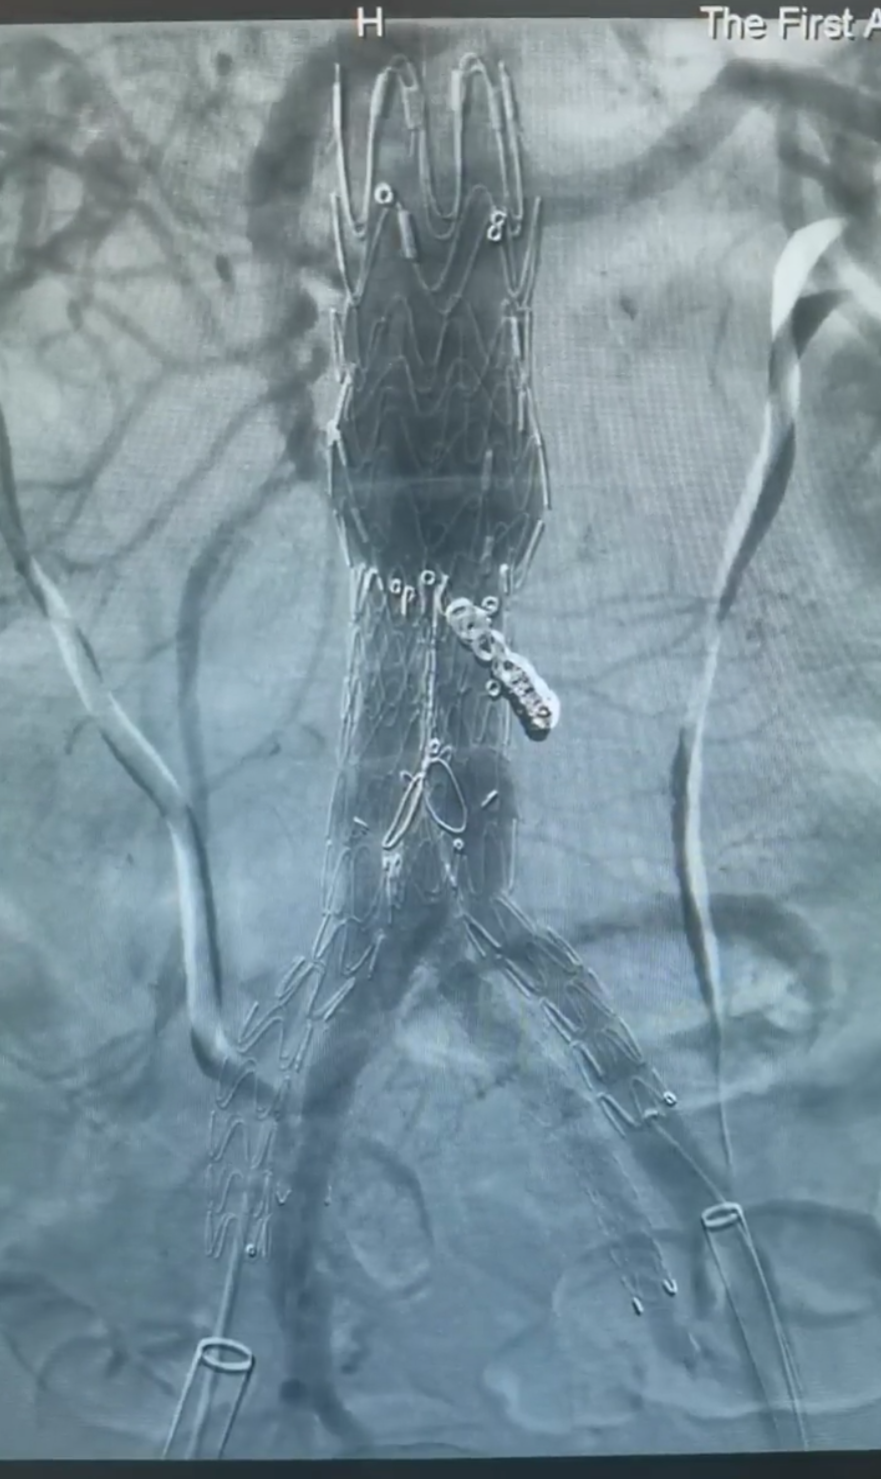

A:术前造影;B:XJZDF34120改装;C:肠下7mm,栓塞;D:主体支架释放

右侧IBD主体到位,超选、测量并导入右侧髂内支架;左侧IBD支架到位,超选、测量并导入左侧髂内支架